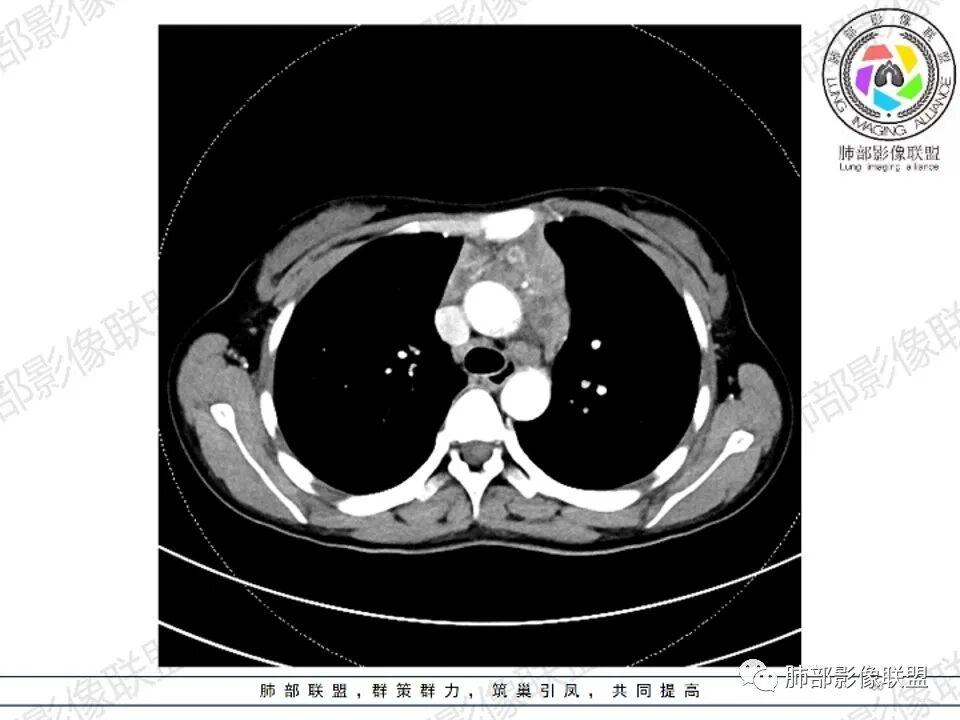

女,27,间断头晕、乏力3年,左眼视物模糊2月。贫血。胸部CT:前纵隔不规则肿块,多结节融合,边界不清,沿主动脉及肺动脉间隙生长,平扫密度欠均匀,增强扫描可见多发低密度坏死,纵隔血管供血穿行,腋窝多发大小不等淋巴结肿大。考虑恶性病变,胸腺癌?肉瘤?淋巴瘤?鉴别胸腺瘤、结节病等。

临床:年轻女性,慢性病程,多系统病变,头晕,贫血,视物模糊。

CT:定位纵膈病变,前中纵隔多发肿块,质软,塑形,密度不均匀,边界清楚。增强不均匀强化,坏死边界清楚,血管漂浮征。双侧腋下多组淋巴结肿大,明显异常强化。

考虑淋巴瘤可能。